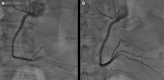

Case summary: The case of a 59-year-old man who underwent conservative mitral valve surgery with tricuspid valve annuloplasty is presented. The early post-operative period was complicated by acute coronary syndrome with inferior persistent ST-segment elevation. A coronary angiogram confirmed critical RCA hazy lesions, raising the suspicion of coronary kinking. To confirm the underlying mechanism for these lesions and determine the best treatment strategy, endocoronary imaging was performed, revealing coronary kinking of the RCA. Based on the persistent acute ischaemia, a long-lasting drug-eluting stent (DES) was implanted in the lower and upper knees of the RCA. After angioplasty, electrocardiography showed regression of the ST-segment elevation. Ten days later, coronary angiography and optical coherence tomography showed good results. The patient recovered from his myocardial infarction.